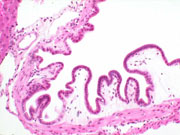

Gallbladder, submucosal edema. This change represents a sporadic finding in mice.